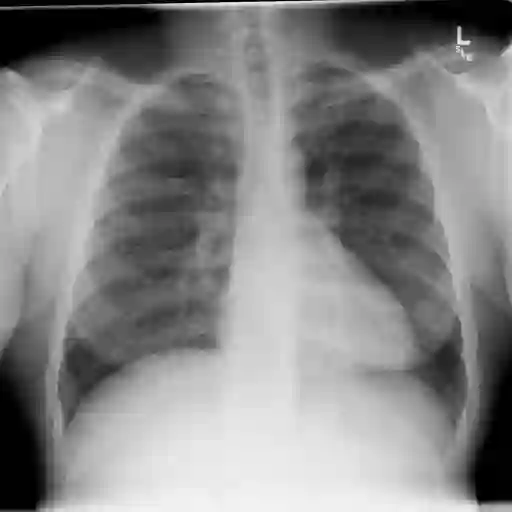

Medical imaging plays a pivotal role in diagnosis and treatment in clinical practice. Inspired by the significant progress in automatic image captioning, various deep learning (DL)-based methods have been proposed to generate radiology reports for medical images. Despite promising results, previous works overlook the uncertainties of their models and are thus unable to provide clinicians with the reliability/confidence of the generated radiology reports to assist their decision-making. In this paper, we propose a novel method to explicitly quantify both the visual uncertainty and the textual uncertainty for DL-based radiology report generation. Such multi-modal uncertainties can sufficiently capture the model confidence degree at both the report level and the sentence level, and thus they are further leveraged to weight the losses for more comprehensive model optimization. Experimental results have demonstrated that the proposed method for model uncertainty characterization and estimation can produce more reliable confidence scores for radiology report generation, and the modified loss function, which takes into account the uncertainties, leads to better model performance on two public radiology report datasets. In addition, the quality of the automatically generated reports was manually evaluated by human raters and the results also indicate that the proposed uncertainties can reflect the variance of clinical diagnosis.

翻译:医学成像在临床实践的诊断和治疗中发挥着关键作用。在自动图像说明的重大进展的启发下,提出了各种基于深层次学习(DL)的方法,为医疗图像生成放射学报告。尽管取得了令人乐观的成果,但先前的工作忽略了模型的不确定性,因此无法为临床医生提供生成的放射学报告的可靠性/信心,以协助其决策。在本文件中,我们提出了一个新颖的方法,以明确量化基于DL的放射学报告的视觉不确定性和文字不确定性。这种多模式的不确定性可以充分捕捉报告层面和句子层面的模型信任度,从而进一步利用这些方法来权衡损失,以进行更全面的模型优化。实验结果表明,拟议的模型不确定性定性和估算方法能够为生成放射学报告提供更可靠的信心分数,以及考虑到不确定性的修改后的损失功能,使两个公共放射学报告数据集的模型性表现更好。此外,自动生成的报告的质量由人手动评估,结果还表明,拟议的不确定性可以反映临床诊断的差异。